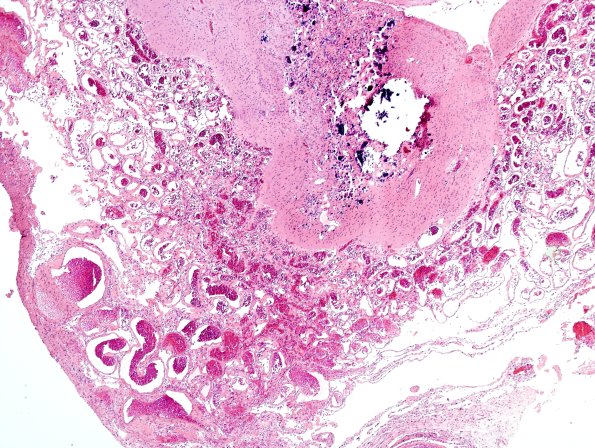

5C4 Encephalocoele (Case 5) H&E 3

5C4,5 Patches of calcifications are prominent. (H&E)